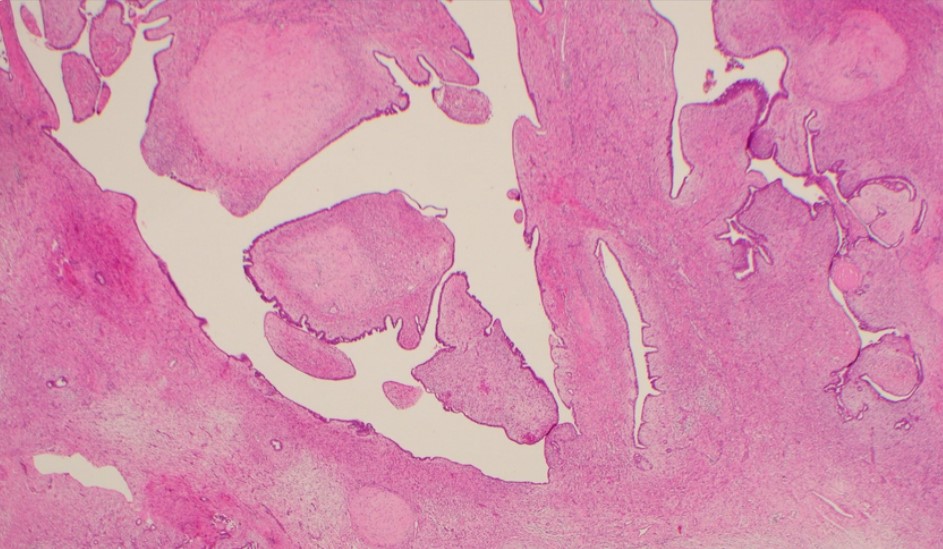

“Phyllodes tumours are rare fibroepithelial breast tumours that can be difficult to diagnose and manage, with a spectrum ranging from benign to malignant”.

Professor O’Toole has dedicated much of her research to understanding these uncommon cancers, with a special focus on phyllodes tumours.